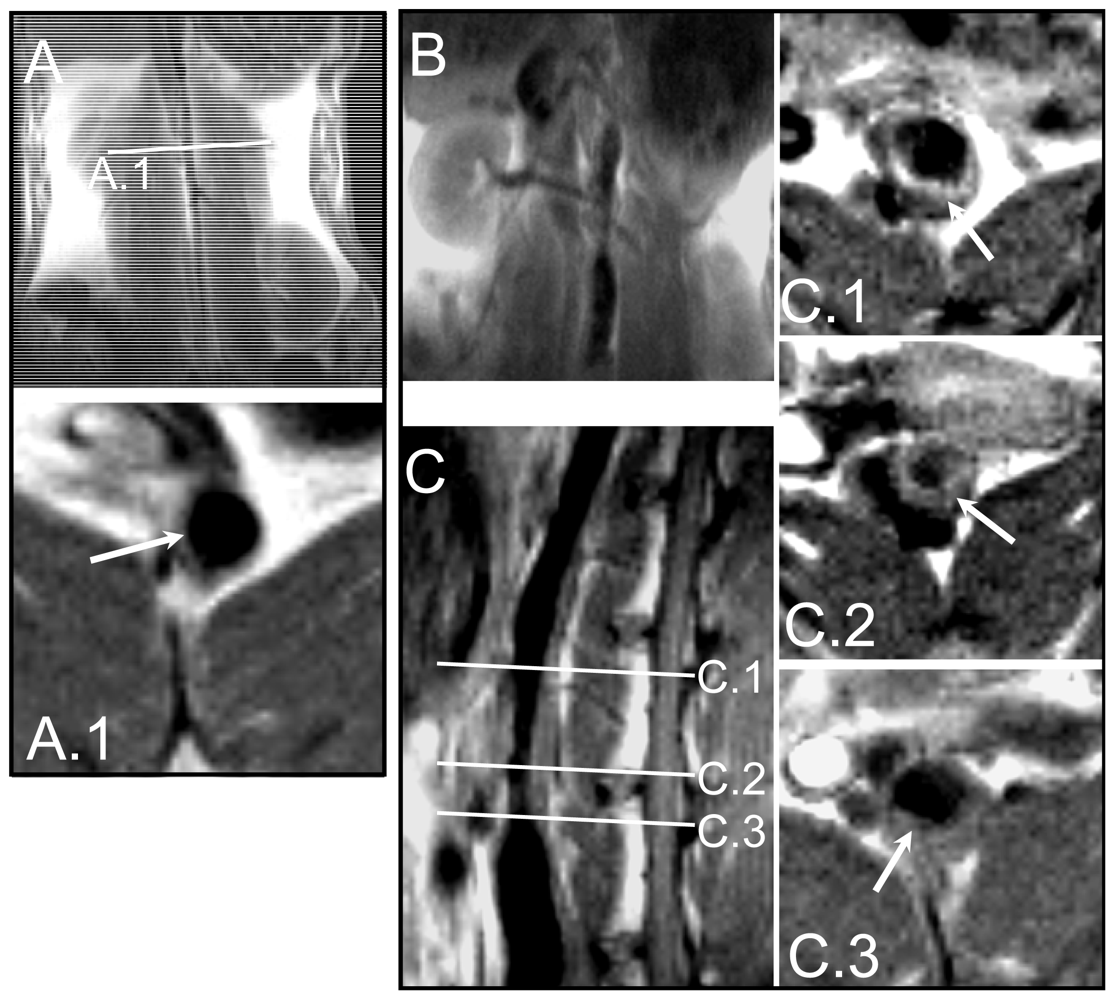

2. Results and Discussion

2.1. Rabbit model of Atherosclerosis

3.1. Animal Model

3.2. Magnetic Resonance Imaging